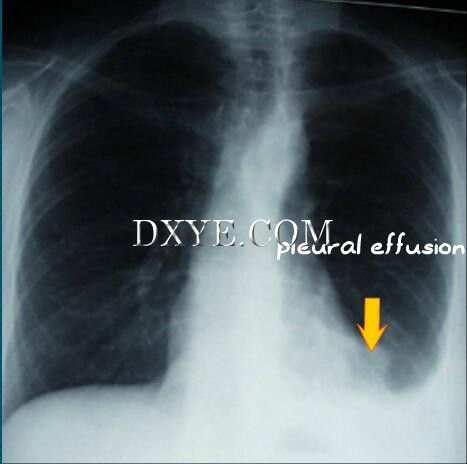

If pleural effusion occurs, it is generally minimal, limited to the filling of the pleural cul-de-sac. No treatment is required other than prescribed respiratory exercises.